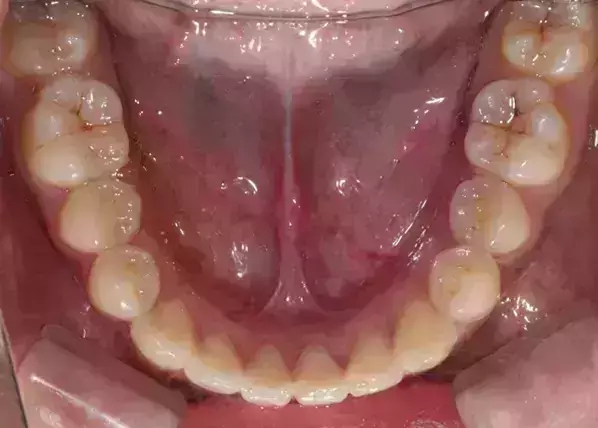

Damon 病例分享:安氏 II 類(lèi)二分類(lèi)露齦笑的矯治(董一磊)

治療前后對(duì)比